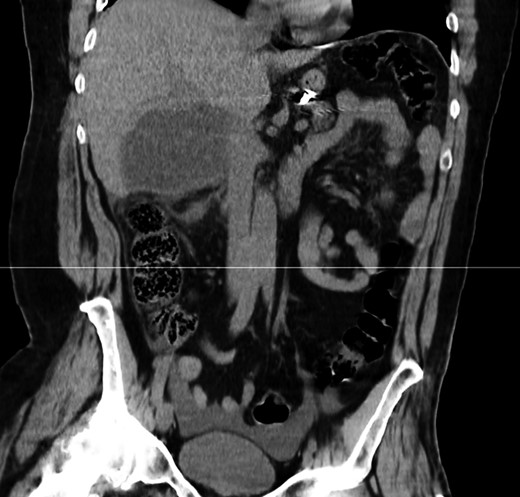

On clinical examination he was distressed, his abdomen was slightly distended with diffuse tenderness, guarding and rebound tenderness. Bowell sounds were present. His blood pressure was 137/81 mmHg, pulse rate 77 beats/minute and body temperature 38.1°C. The rest of the clinical examination was unremarkable. Blood tests showed acute inflammation, with a white cell count of 12 800 × 103/μl, with 90.2% neutrophils, C-reactive protein of 5.9 mg/dl and a haemoglobin of 13.4 g/dl. Hepatobiliary and pancreatic enzymes were normal. The INR was 1.2. Chest and abdominal radiographs were normal. Computed tomography (without intravenous contrast) revealed a 9 cm hypodense lesion in segment VI of the liver and free fluid in the peritoneal cavity (Figs 1 and 2).

CT scan—coronal view: hypodense lesion in segment VI of the liver.